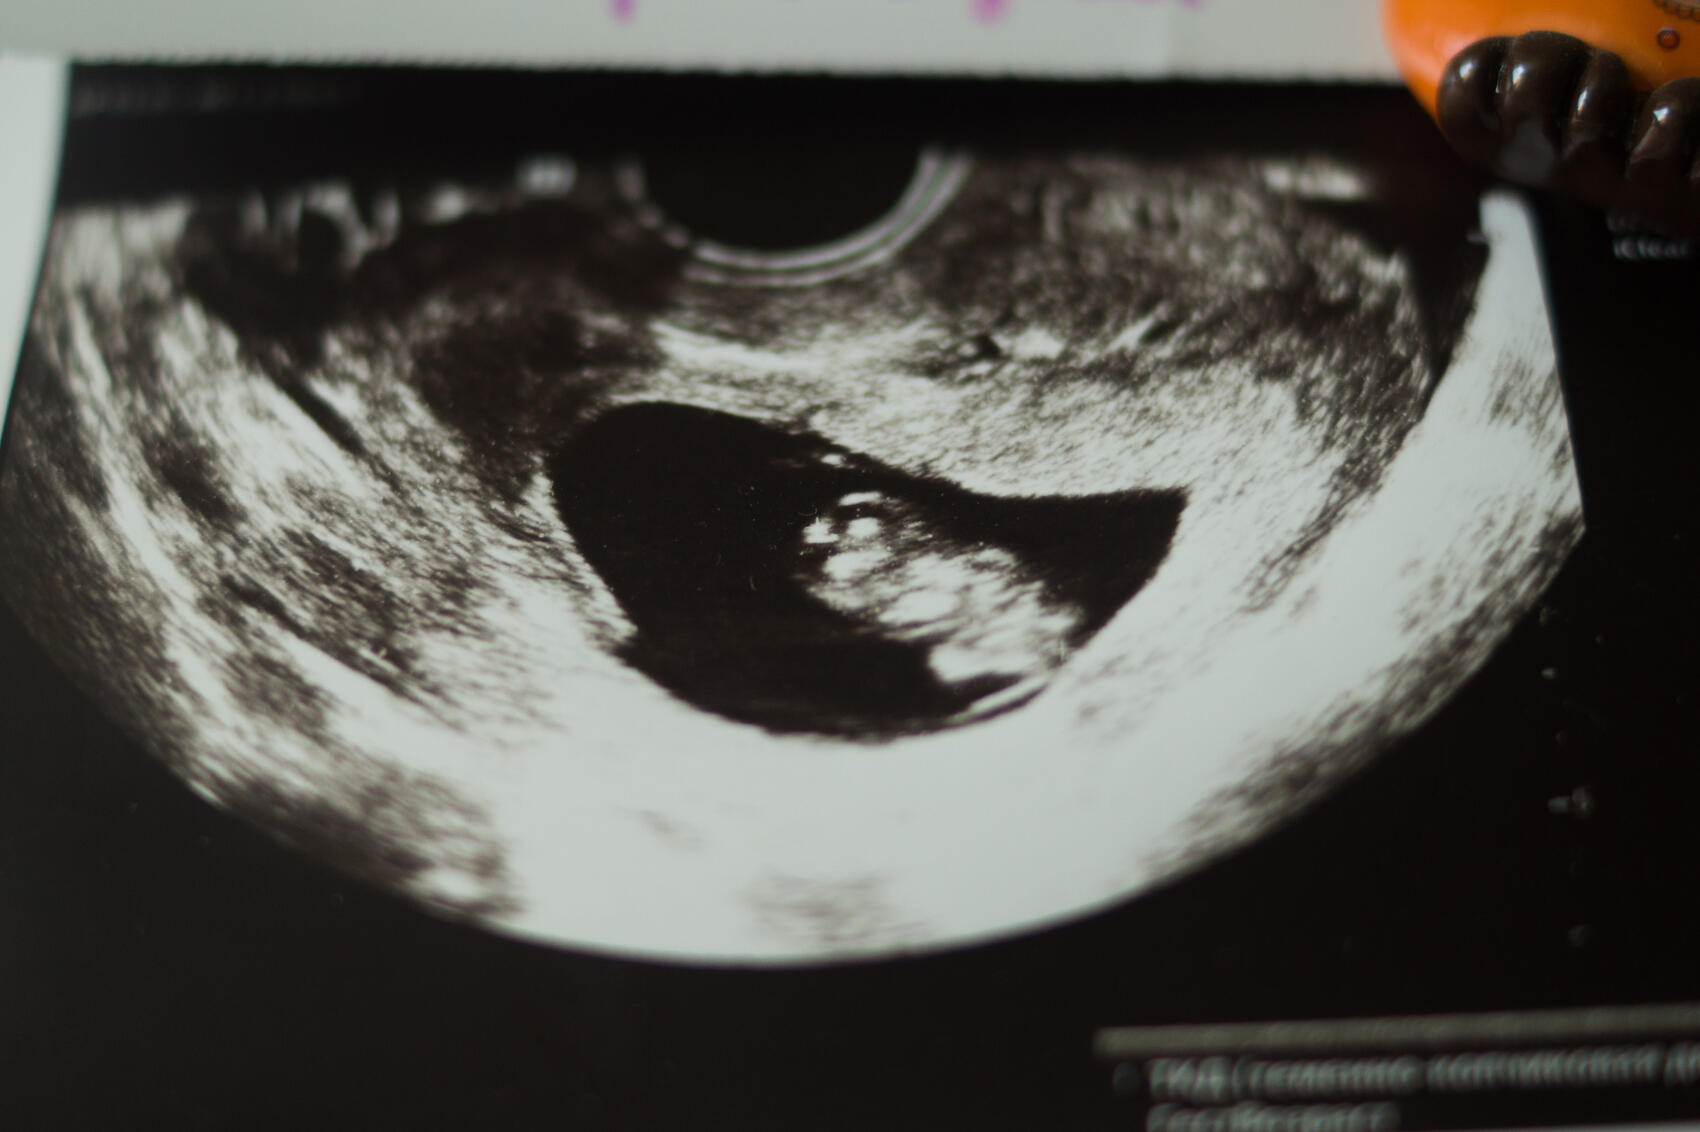

Фото: Елена Елизарова / It’s My City

«Мы предлагаем сегодня в качестве шага в сторону ограничения абортов, разумного, мы понимаем, что государство может лишь постепенно идти в эту сторону, но мы должны двигаться в этом направлении. Искусственное прерывание беременности по желанию женщины должно проводиться при наличии добровольного согласия не только самой женщины, но и ее мужа. Необходимо, чтобы оно проводилось после обязательного доабортного психологического консультирования, и это должно быть закреплено в законе, а также ультразвукового исследования, демонстрации сердцебиения плода человека», — говорит Лукьянов.